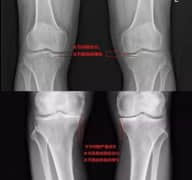

得了骨性关节炎,膝关节间隙变窄是怎么回事?